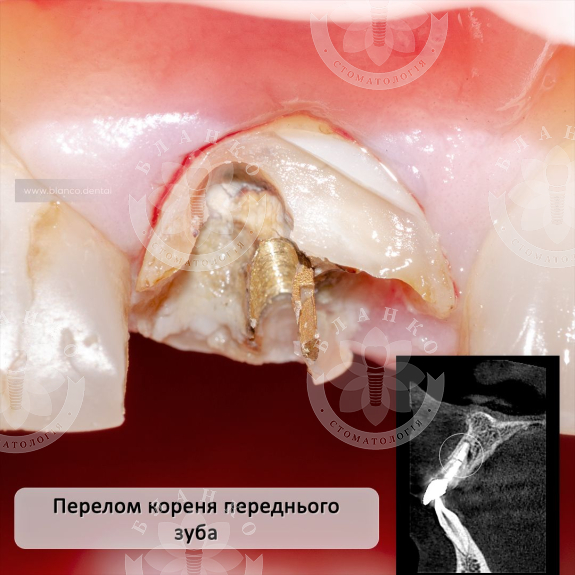

На компьютерной томограмме определяется фрактура ( перелом ) корня зуба. Такие зубы восстановлению не подлежат.